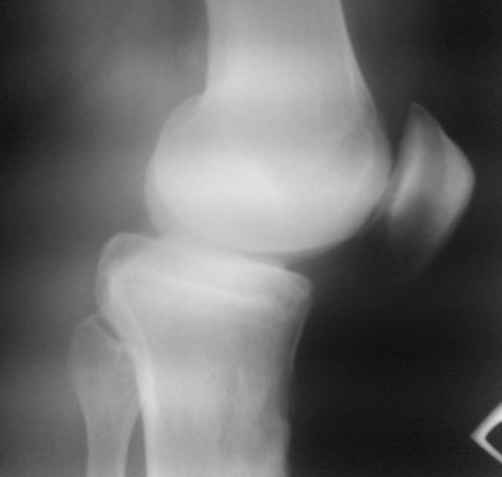

По видимому, тогда было повреждение задней крестообразной связки,

рекурвация голени стала устойчивой, плато имеет неправильный угол

наклона, а в верхней трети большеберцовой кости формируется маршевый

перелом.

Объективно. Боли при пальпации нет, движения практически в полном

объеме. Рекурвация внешне совершенно очевидная. Положение голени

устойчивое.

Растущая киста Бейкера говорит о начале декомпенсации со стороны

сустава, как я понимаю.

Что мы можем предложить пациенту. Ваши прогнозы по развитию маршевого

перелома. Стоит ли сейчас предлагать коррекцию рекурвации. Что делать

с «задним выдвижным положением», ибо это уже не

«ящик». Нет даже колебания вперед-назад.

простите, мне и самому кажется, что качество снимков не лучшее.